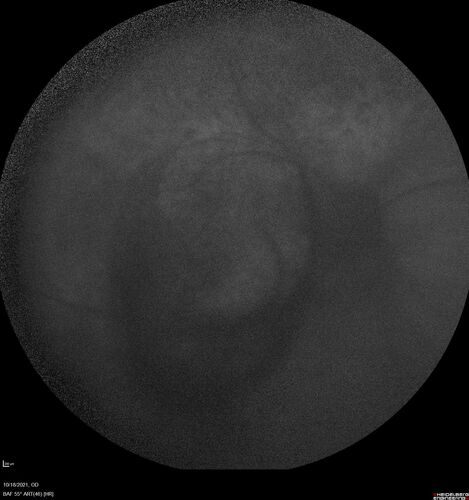

Severe Syphilitic Placoid Chorioretinitis

68 year old man 3 months ago the vision started fading in both eyes.  Just sitting here he can see some light out of his right eye. The patient denies any recent illness or travel.

VA: OD: LP, OS: 4/200

IOP: 9, 13

Anterior segment: 1+ cell/ 2+ flare OU and 2+ NS and anterior vitreous cells

Labs Reactive RPR 1:256, FTA-ABS - reactive - Patient was admitted to hospital for IV PCN and recovered vision almost completely in the left eye and some in the right eye.